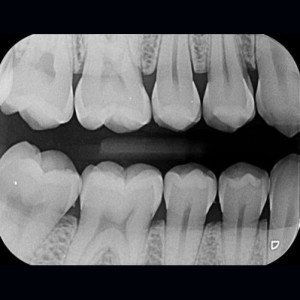

SERVICIOS 2D